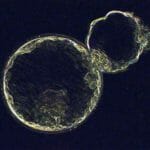

Hatching Blastocyst

Early Hatching Embryo

Hatched Blastocyst